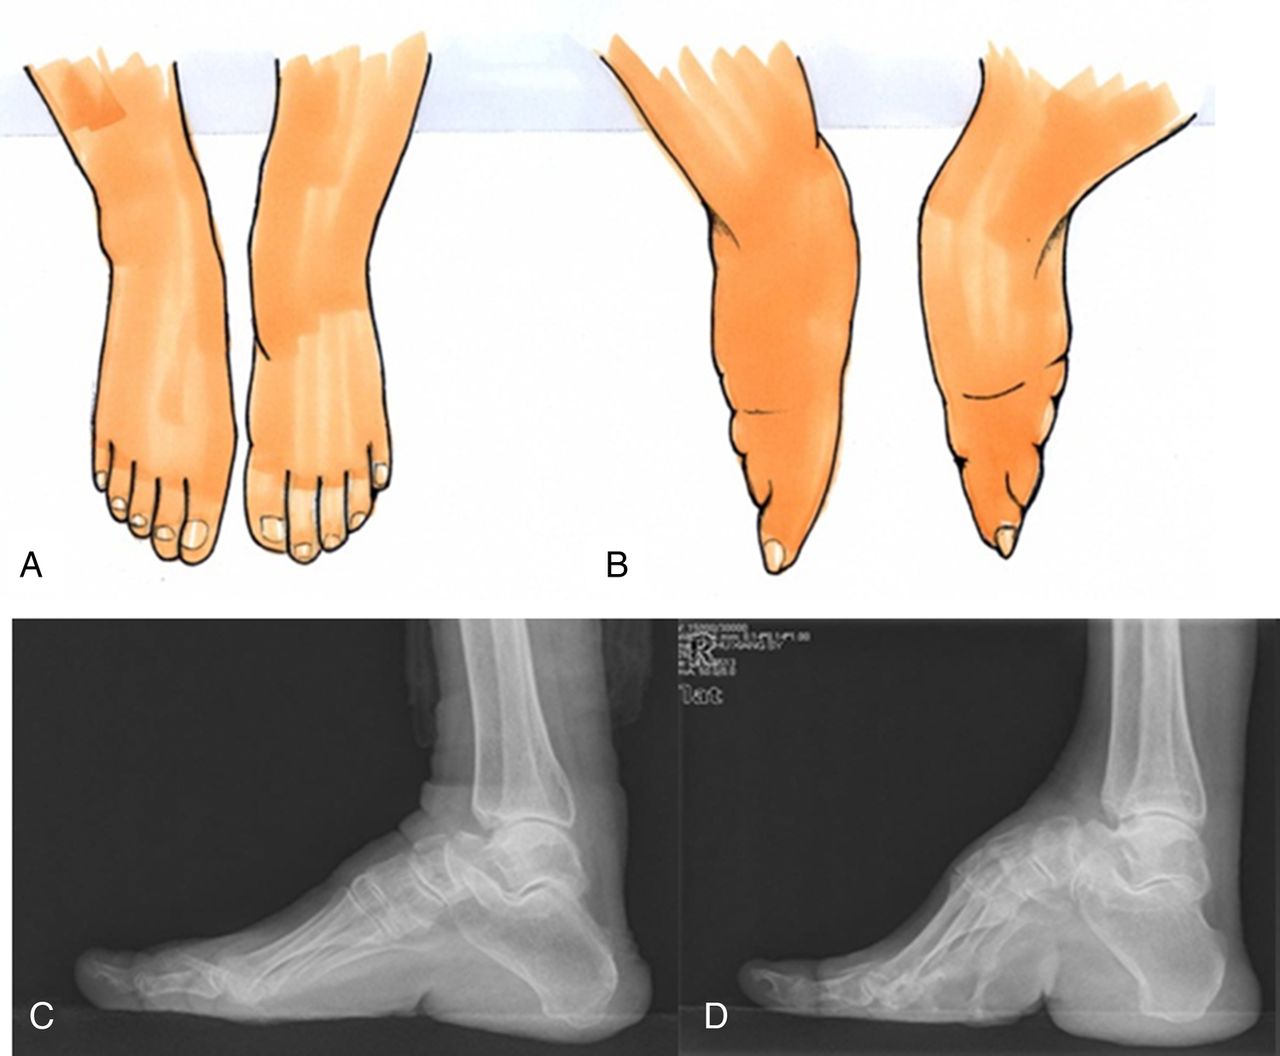

chinese foot binding Google Search Interesting history, Women in Foot Binding China Reason updated on november 21, 2019. it was an excruciatingly painful practice that maimed the feet of millions of chinese girls and women for. foot binding was a cruel practice that was prevalent in ancient china, particularly during the song dynasty, from the 10th to the 13th centuries. For centuries, young girls in china were subjected to an. Foot Binding China Reason.

(FootBinding) Lecture FootBinding Footbinding, a cultural Foot Binding China Reason updated on november 21, 2019. For centuries, young girls in china were subjected to an extremely painful and. it was an excruciatingly painful practice that maimed the feet of millions of chinese girls and women for. foot binding was a cruel practice that was prevalent in ancient china, particularly during the song dynasty, from the 10th to. Foot Binding China Reason.